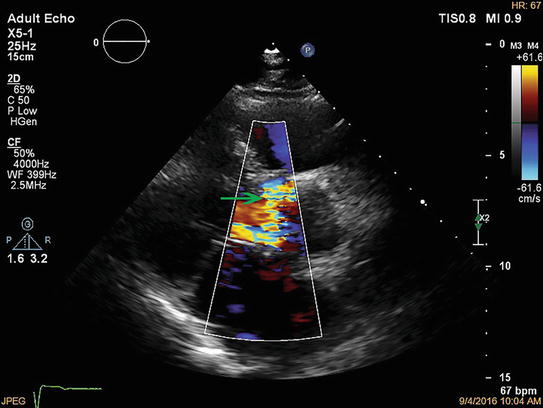

Steps In Paravalvular Leak Closure Echographic Perspective A 3d Echo Download Scientific Diagram Percutaneous closure of paravalvular leak after transcatheter valve implantation in mitral annular calcification by guillaume leurent et al.